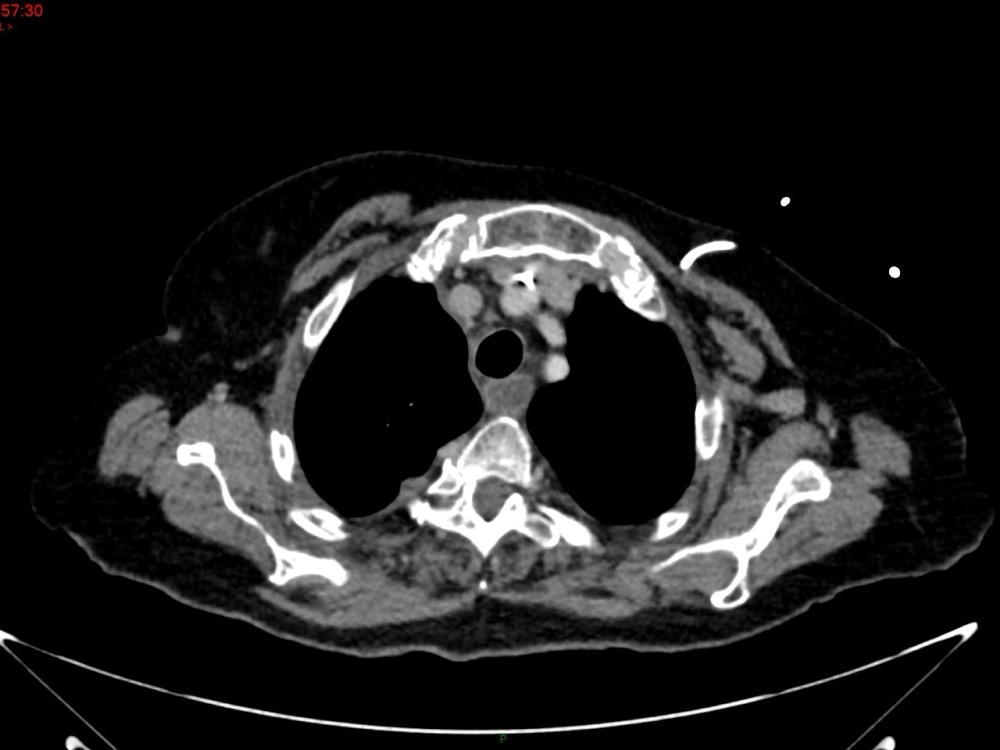

Marie Pauline Talabard 11/01/2023